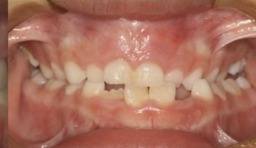

O tratamento que tem como objetivo tratar a má-oclusão através de recursos terapêuticos (aparelhos removíveis) que utilizam estímulos funcionais precocemente através de orientação mastigatória, desgaste seletivo, acréscimo às superfícies dentárias.